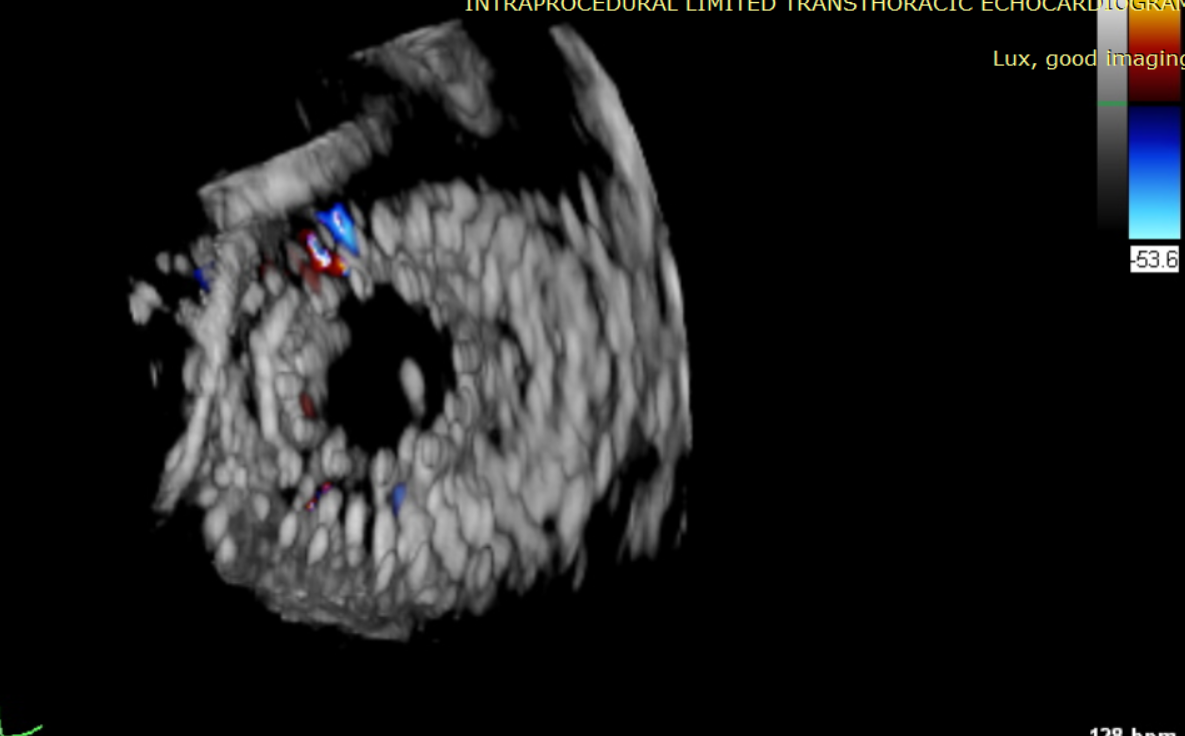

近日,美國紐約Montefiore醫(yī)學中心(Montrefiore Medical Center)的Azeem Latib教授團隊成功應用LuX-Valve Plus經(jīng)血管三尖瓣置換系統(tǒng)為兩位三尖瓣大量反流的患者完成三尖瓣置換手術。術后超聲顯示人工三尖瓣植入穩(wěn)定,瓣葉啟閉良好,僅殘余微量瓣周漏?;颊哂谑中g室即刻拔除氣管插管,血流動力學改善顯著。此次手術是LuX-Valve Plus于紐約的首次臨床應用,治療效果優(yōu)異。

術后Azeem Latib教授對LuX-Valve Plus經(jīng)血管三尖瓣置換系統(tǒng)的器械性能和治療效果大為稱贊,并且認為LuX-Valve Plus的手術體驗非常好。從治療效果來看,術后即刻超聲顯示三尖瓣反流幾乎完全消失,血流動力學改善顯著,患者恢復快。在面對復雜解剖結構、超聲影像質量不佳、有起搏導線干擾時,Lux-Valve Plus也體現(xiàn)了極強的適應性。Thomas Modine教授參與了術中指導,他同樣再次肯定了LuX-Valve Plus術中操作的便捷性,認為LuX-Valve Plus容錯率高,對術中影像的依賴小,并表達了后期希望可以更多地應用LuX-Valve Plus三尖瓣置換系統(tǒng)于臨床實踐,讓更多的三尖瓣重度反流患者盡早獲益,改善預后。